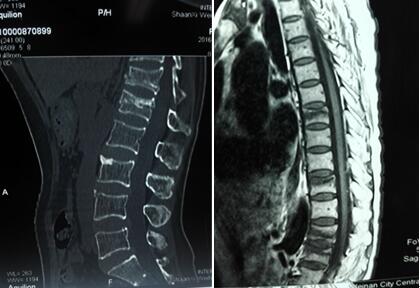

术前三维CT+胸椎MR